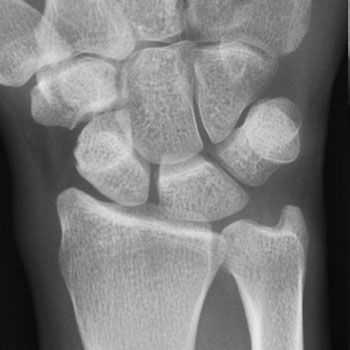

Рентгенография не помогает в диагностике БДК, однако может помочь исключить другие патологии: переломы пястных костей и остеоартрозы межпястных суставов, артрозы и прочее.